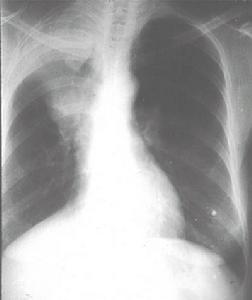

小儿肺泡性蛋白沉积症(pulmonary alveolar proteinosis,PAP)又称为肺泡磷脂沉着症,是一种原因不明的少见慢性肺疾病,为亚急性、进行性呼吸功能不良,肺泡内积聚富有黏蛋白物质及脂质的疾病。小儿肺泡性蛋白沉积症有致死性的先天性肺泡性蛋白沉积症和后天获得性的肺泡性蛋白沉积症。小儿肺泡性蛋白沉积症特点为肺泡内有富含脂质的糖原(PAS)染色阳性蛋白物质沉着,病在肺泡腔和气道内堆聚过量,致使肺的通气和换气功能受到严重影响,导致呼吸困难。[1]